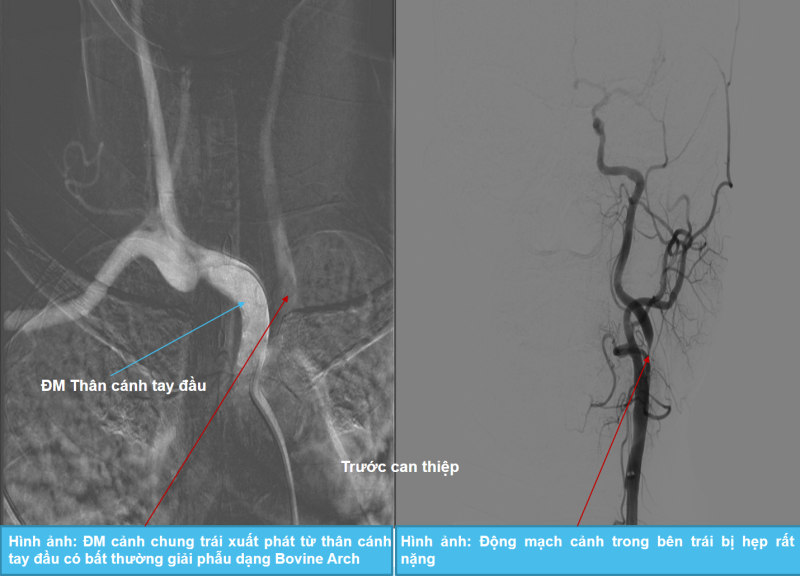

Bệnh nhân được chỉ định chụp mạch xóa nền DSA, cho thấy động mạch cảnh trong bên trái bị hẹp rất nặng, trong khi động mạch cảnh trong bên phải bị teo nhỏ – nguyên nhân chính gây thiếu máu não – kèm bất thường giải phẫu mạch máu dạng Bovine Arch (dạng động mạch cảnh chung trái xuất phát từ thân động mạch cánh tay đầu thay vì từ cung động mạch chủ như bình thường). Các bác sĩ quyết định thực hiện can thiệp đặt stent để tái thông dòng chảy mạch máu não cho bệnh nhân.

Dưới sự hỗ trợ của hệ thống chụp mạch số hóa xóa nền DSA, Thạc sĩ, bác sĩ Giáp Hùng Mạnh cùng ê kíp can thiệp đã tiến hành nong động mạch cảnh trong bên trái bị hẹp và đặt stent thành công, giúp mở rộng lòng mạch hiệu quả, phục hồi lưu lượng máu lên não cho bệnh nhân.